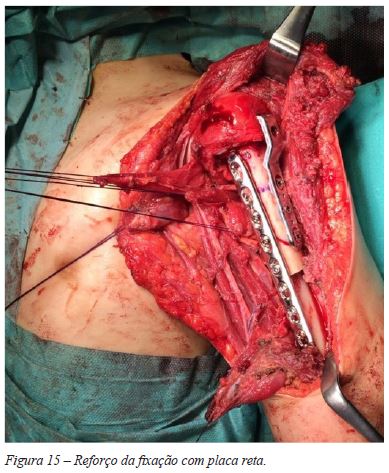

Introduziu-se a lâmina de bisturi na fise, de forma a separar a epífise e metáfise umerais proximais, conseguindo-se uma ressecção monobloco, sem visualização macroscópica do tumor (Figura 13). Colheram-se amostras de tecido ósseo do topo distal do úmero e da zona fisária residual na epífise umeral, tendo-se enviado o material para estudo anatomo-patológico e confirmação das margens de ressecção. De seguida, foi realizada a preparação de enxerto alógeno de úmero - com confecção de corte para encastoar no úmero nativo distalmente e para melhor adaptação a nível epífise. Fixou-se com lâmina-placa 90º, mantendo o cravo proximal para orientação da mesma (Figura 14). A fixação foi reforçada com a aplicação de uma placa recta LCP 3,5mm num plano ortogonal relativamente à outra placa (Figura 15). Ambas as placas foram aplicadas em compressão. Não se registaram intercorrências peri-operatórias.